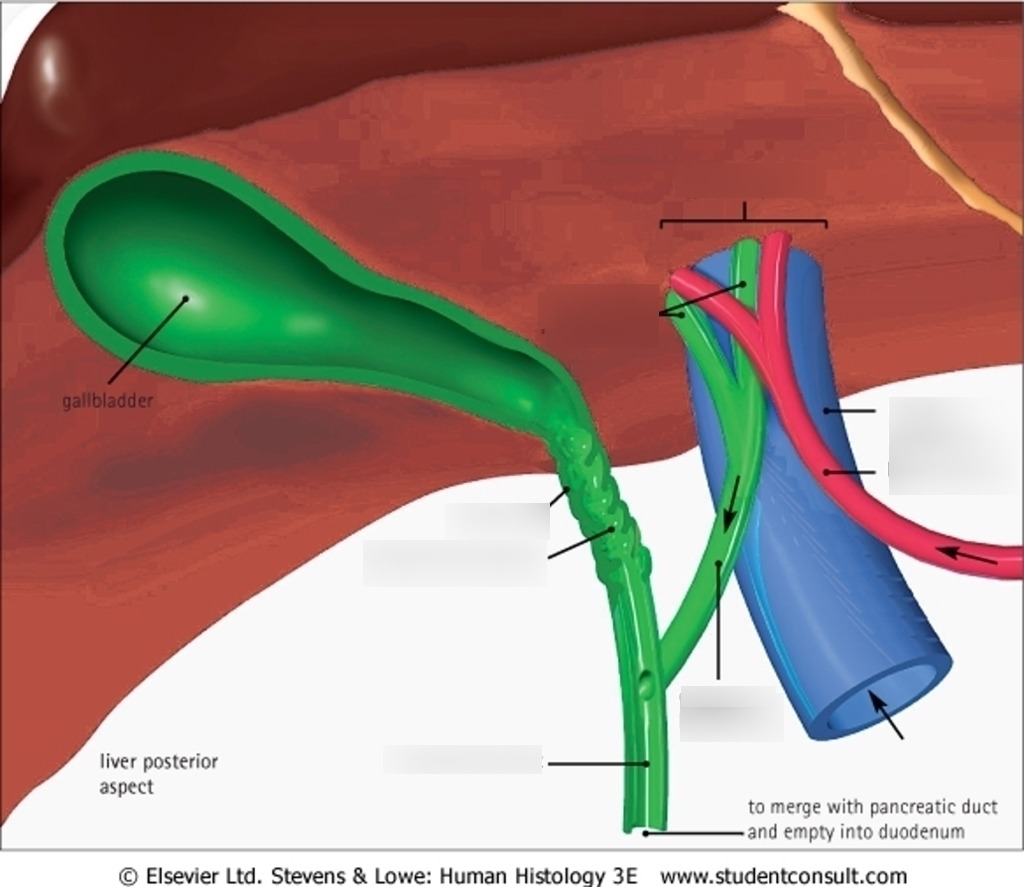

Fundus of gallbladder

orange highlight

Body of gallbladder

green highlight

Neck of gallbladder

yellow highlight

Cystic duct

pink highlight

Left hepatic ducts

Right hepatic ducts

Common hepatic duct

Common bile duct

Duodenal papilla within duodenum